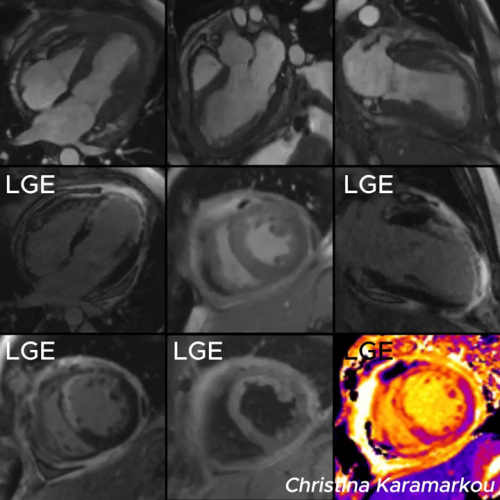

Diagnosis and Treatment of Rare Cardiac Conditi...

Mrs. Lim, a 58-year-old Malaysian patient, was initially misdiagnosed with idiopathic pulmonary arterial hypertension (IPAH). After a comprehensive diagnostic evaluation in Beijing, she was correctly diagnosed with a double-chambered right...